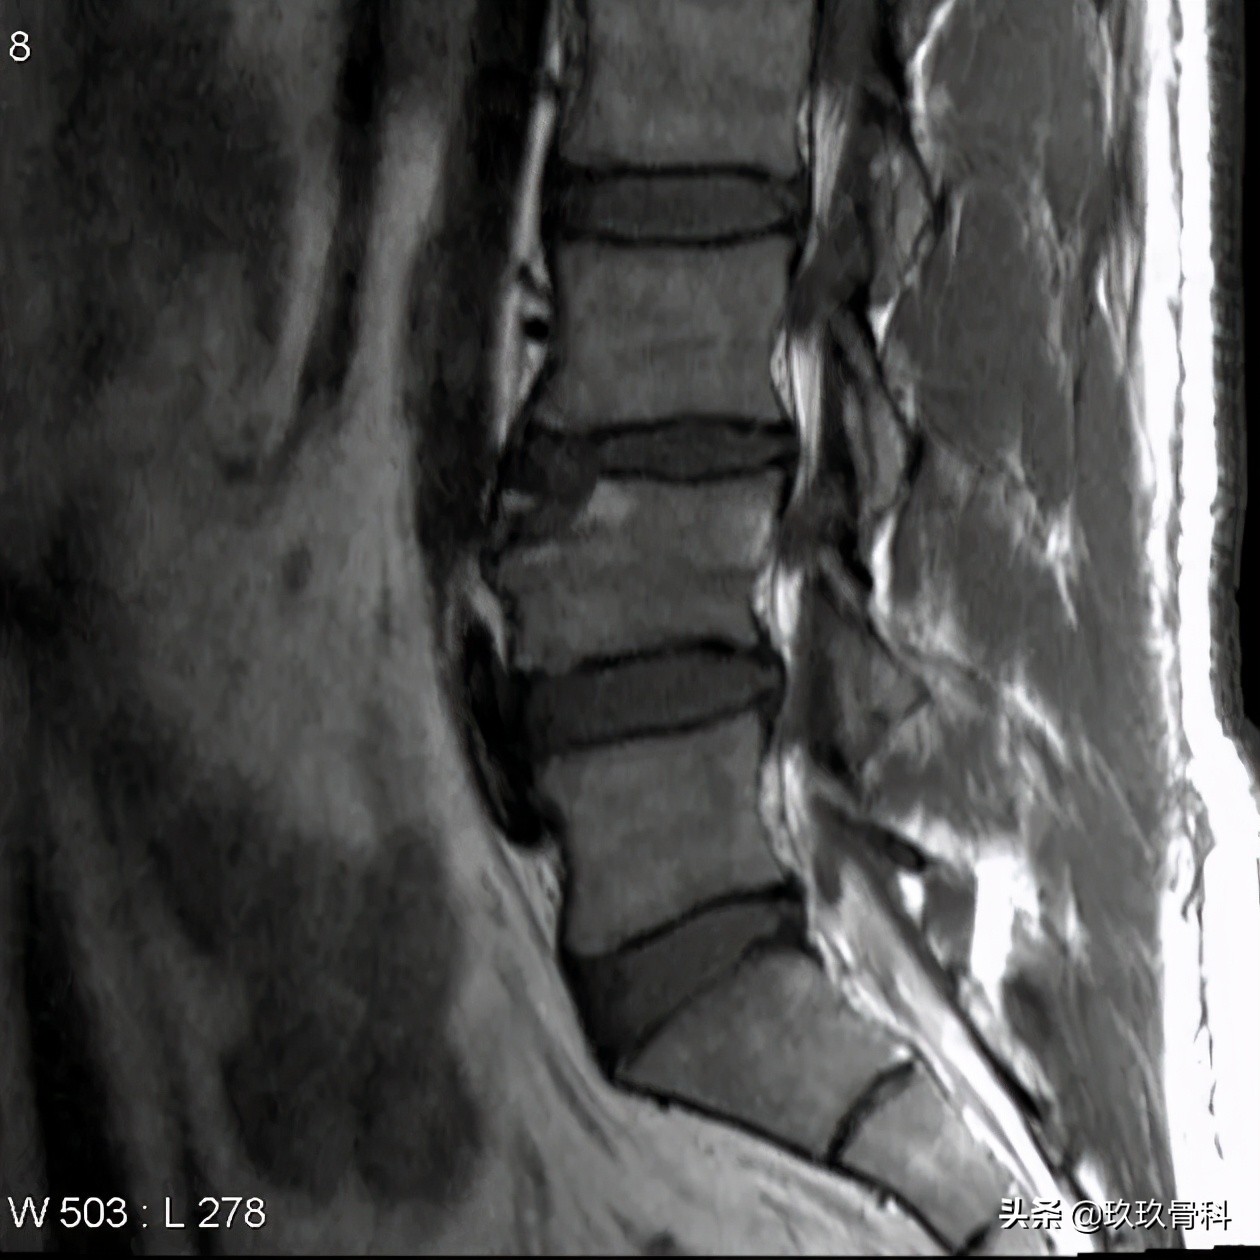

患者伴有长时间的腰背部疼痛史。L4椎体前上缘局灶性骨质缺损,区域内可见一游离的骨性信号。

MRI显示 游离的骨块呈长T1短T2信号,游离骨块与椎体间缺损区与同层椎间盘等信号。

L4-5椎体前上缘局灶性骨质缺损区,不规则,外形欠光整,缺损区呈与同层面椎间盘信号或密度相似,患者无症状或伴有腰痛病史, 要考虑到椎缘骨的可能 。